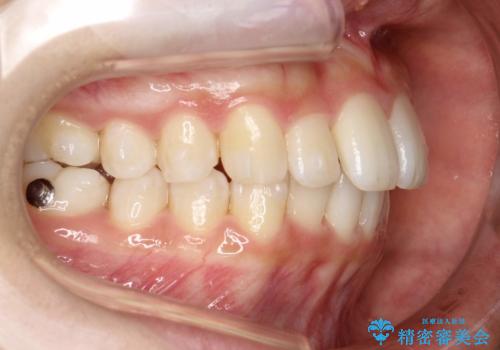

Invisalign インビザラインによる軽度なガタつきの改善

- 奥歯の位置関係はそこまで大きくいじらず、前歯群のみでガタつきの改善を計画しました

奥歯の位置関係に改善の余地はありますが、機能的に問題のない cusp to fossa の関係で咬めているため、前歯のガタつきを前歯のみで改善するというシンプルな計画で、短期間で治療を終了させました。